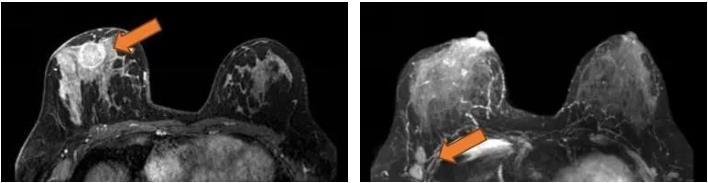

2021.7.7乳腺MRI:右乳外上象限肿物(BI-RADS-6)3.1cm×1.9cm×3.0cm,右腋窝见肿大淋巴结,M灶可能。

右乳外上象限见不规则肿块,呈长/稍长T2、等T1信号,DWI呈高信号,ADC图信号减低,ADC值约0.863,增强扫描明显强化,TIC呈Ⅲ型,大小约3.1×1.9×3.0cm,邻近皮肤增厚,皮下脂肪层模糊,另肿块外侧旁见小肿块影,增强明显强化,与外上象限肿块相连。右侧腋窝见肿大淋巴结。

图3. 乳腺MRI

(3 cycle 后)2021.9.22 复查乳腺MRI示:右乳肿块较前减小14mm×9mm×18mm。

图7. 乳腺MRI